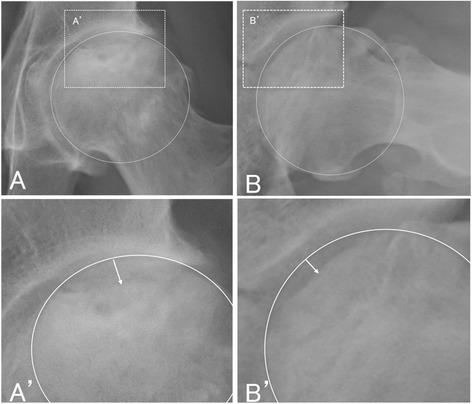

We had previously established concentrated autologous bone marrow aspirate transplantation (CABMAT), a one-step, low-invasive, joint-preserving surgical technique for treating osteonecrosis of the femoral head (ONFH). The present study aimed to evaluate the effects of CABMAT as a hip preserving surgical approach, preventing femoral head collapse in asymptomatic ONFH.

Secondary collapse of the femoral head was observed in 6/10 hips and 5/10 hips with osteonecrosis of types C1 and C2, respectively. Total hip arthroplasty was performed in 9.6% of patients (3/31 hips), at an average of 33 months after surgery. Clinical symptoms improved after surgery, and the secondary collapse rate at a mean of 5.8 years after CABMAT was lower than that reported in several previous studies on the natural course of asymptomatic ONFH.